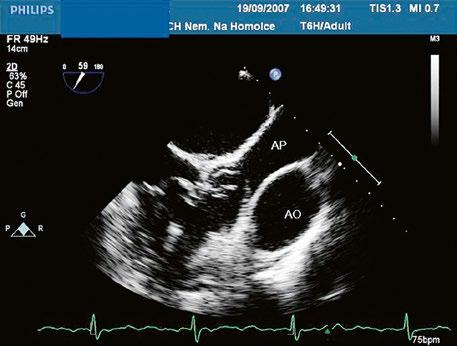

Obr. 45.1 Defekt septa síní typu II v TEE

AO – aorta, DDŽ – ústí dolní duté žíly do pravé síně, defekt septa síní je označen křížky, má předozadní průměr 22 mm, zasahuje blízko zadní stěny levé síně, LS – levá síň, PS – pravá síň

Obr. 45.2 Defekt septa síní typu II v TEE

AO – aorta, ASD – defekt septa síní typu secundum označen šipkou, zelenými křížky je označen malý přední rim k aortě, LS – levá síň, PS – pravá síň